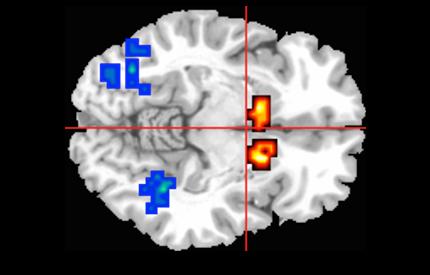

All participants were studied in an MRI scanner while performing a memory task which engages three regions of the brain known to be involved in psychosis.

As expected, the brain activity in the participants at risk of psychosis was abnormal compared to the healthy participants. However, among those who had cannabidiol, the abnormal brain activity was less severe than for those who received a placebo, suggesting cannabidiol can help re-adjust brain activity to normal levels.

The influence of cannabidiol on these three brain regions could underlie its therapeutic effects on psychotic symptoms.